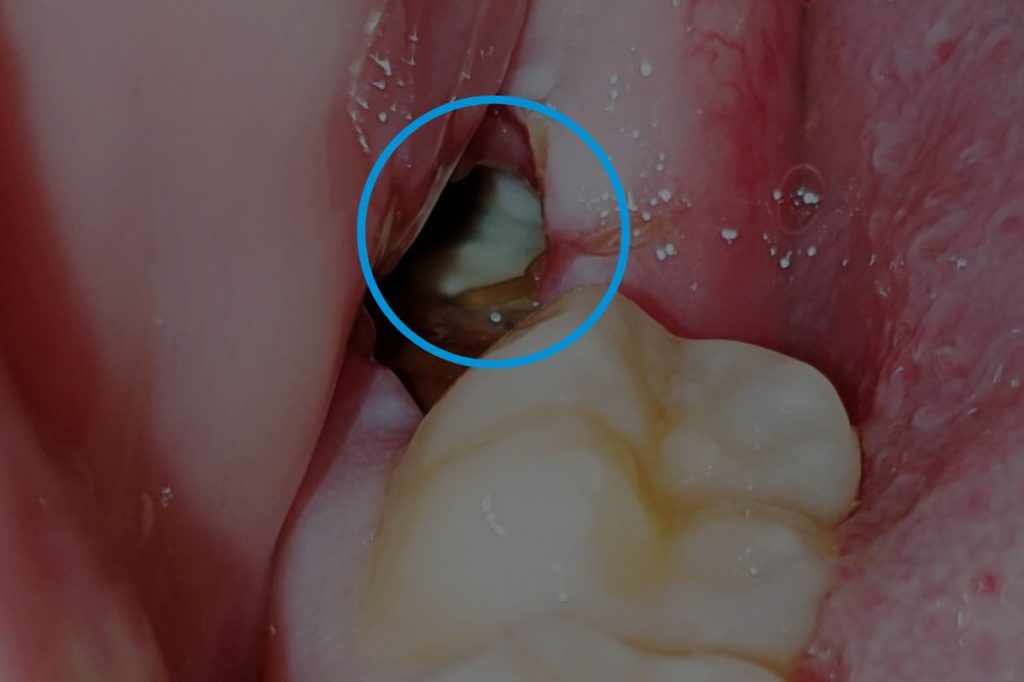

Dry Sockets

• A common issue where the blood clot becomes dislodged, exposing the bone.

• This leads to a dull ache around the third to fifth day after surgery.

• Treatment involves medicated dressings for pain relief and may require multiple visits to replace the dressing.